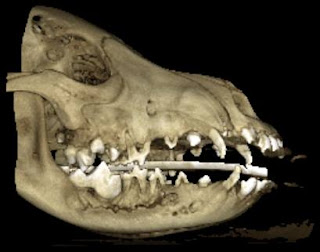

Waudelle tuli kesällä outo mätäpaise leukaan jonka kaverini huomas ja siitä jouduttiin käymään Anidentissa Veikkolassa ja sielä ei spesialistit tienny mikä moinen on ja epäiltiin tulehdusta tai syöpää. Koepalat lähettiin patologeille Englantiin ja sielä 10 patologia tutki koepalat mutta hekään ei osanneet sanoa mikä tulehdus se oli ja mistä tullut. Se vahvistettiin että syöpä se ei ole. Waude söi kuus viikkoo kovia antibiootteja ja kaks kertaa käytiin Oivassa jälkitarksissa ja viimesellä kerralla tulehdus oli hävinny kokoaan ja kaikki hampaat säästy ja muutenkin ei mitään puolieroa jäänyt terveeseen puoleen. Outo oli koko juttu, mutta pääasia että koira voi hyvin.

Tässä kuvat mitkä Anidentissä otettiin:

Waudelle tuli kesällä outo mätäpaise leukaan jonka kaverini huomas ja siitä jouduttiin käymään Anidentissa Veikkolassa ja sielä ei spesialistit tienny mikä moinen on ja epäiltiin tulehdusta tai syöpää. Koepalat lähettiin patologeille Englantiin ja sielä 10 patologia tutki koepalat mutta hekään ei osanneet sanoa mikä tulehdus se oli ja mistä tullut. Se vahvistettiin että syöpä se ei ole. Waude söi kuus viikkoo kovia antibiootteja ja kaks kertaa käytiin Oivassa jälkitarksissa ja viimesellä kerralla tulehdus oli hävinny kokoaan ja kaikki hampaat säästy ja muutenkin ei mitään puolieroa jäänyt terveeseen puoleen. Outo oli koko juttu, mutta pääasia että koira voi hyvin.

Tässä kuvat mitkä Anidentissä otettiin: